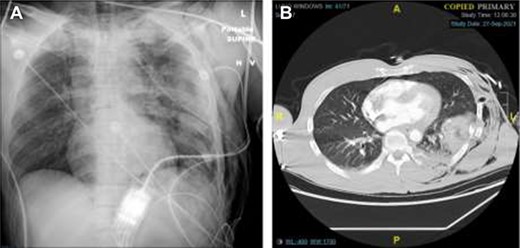

A 47-year-old man was brought to the emergency department by ambulance following a head-on collision with a tree. The patient was the restrained driver, airbags were deployed, and he required a prolonged 30-minute extrication from the vehicle. En route to the hospital, the patient underwent needle decompression of the left chest due to absent breath sounds, and received 1 unit of erythrocytes. He arrived hemodynamically stable, and was immediately sent for imaging. Chest X-ray and computed tomography (CT) revealed a left hemopneumothorax, as well as a left chest subcutaneous emphysema extending to the left abdomen. We also observed trace left pneumomediastinum, left lung contusions, as well as fractures to left ribs 1–12, thoracic and lumbar transverse processes, a cervical articular facet fracture, and a trace left subdural hematoma (Fig. 1). After placing a left chest tube, the patient was admitted to the surgical intensive care unit (ICU) for traumatic brain injury monitoring.

Chest X-Ray and CT imaging showing rib fracture. (A) Chest X-ray and (B) CT showing fractures to the left ribs.